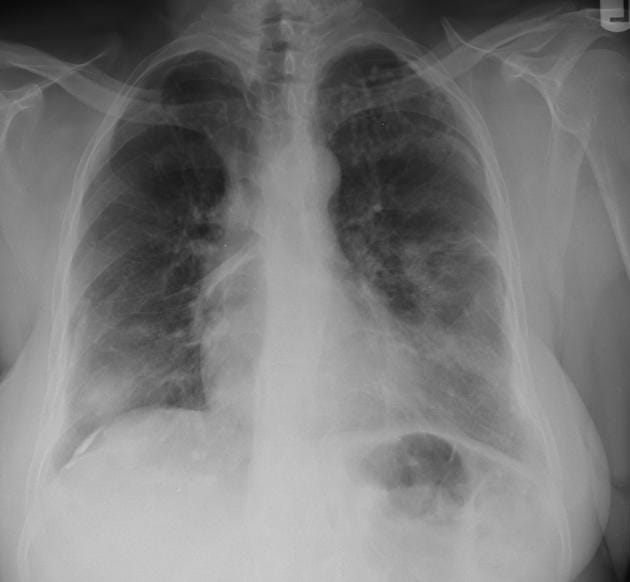

Kryptokokoza płucna

Postać płucna może przebiegać bezobjawowo lub manifestować się przewlekłym kaszlem, odksztuszaniem dużych ilości wydzieliny, dusznością i bólem opłucnowym, a nawet niewydolnością oddechową. Zakażenia objawowe zazwyczaj rozwijają się powoli, w ciągu tygodni, a w przypadku immunosupresji – w ciągu dni. W badaniach obrazowych stwierdza się guzki, nacieki lub zmiany jamiste, niekiedy imitujące gruźlicę lub nowotwór [3]. Rozpoznanie kryptokokozy płucnej zawsze wymaga wykluczenia zajęcia OUN.

Identyfikacja czynnika etiologicznego polega na wykonaniu preparatu bezpośredniego, hodowli na odpowiednich pożywkach, badaniach serologicznych, histologicznych oraz molekularnych [1–3]. Warto wykonać badania obrazowe głowy i klatki piersiowej w celu oceny rozległości choroby i obecności guzków.